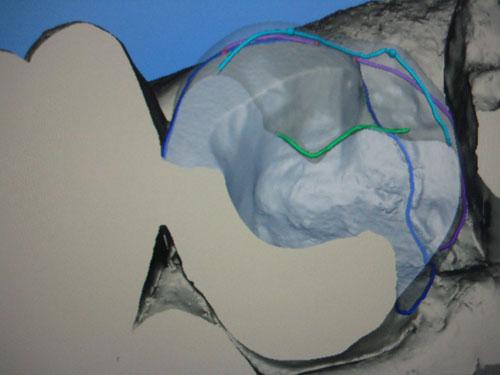

Restauration automatique en mode biogénérique

Ajustage manuel de la morphologie de la dent en mode "Scale"

Visualisation par transparence

Une empreinte du mordu de l'antagoniste (Luxabite(r)) a été effectuée et le mordu est numérisé en place ce qui délimite virtuellement la limite occlusale de reconstitution.

Ajustage manuel de l'intensité des points de contact et de l'antagoniste à l'aide des outils de cire virtuelle (+) (-) ou lissage